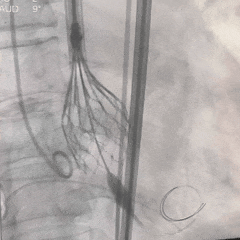

外周血管检查,无损伤

TEE短轴,无瓣周漏

TEE长轴,瓣膜深度可